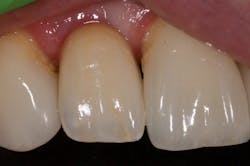

I began centering my consultation appointments on options that subsequently allowed patients to actually sell themselves on the implant treatment modality. I would present the tooth-replacement options of endo/core/crown, extraction/bridge, and extraction/implant ... and then I would explain the pros and cons of each. What I found is that patients overwhelmingly chose the root-replacement option—dental implants—over the old-school (drill-o-dontics) to reconstruct their missing tooth. Patients actually wanted an implant once they were armed with all the complete information they needed to make their decision. Having models on hand that show the difference between each option is highly effective, especially for those patients who are visual learners.

This is the paradigm shift in thinking that initiated big changes in my practice. In 2010, my little office restored 38 implant fixtures. By 2017, we were restoring closer to 200. What a difference! When patients began to realize they had treatment possibilities that may have a better long-term prognosis than the traditional replacement options, implants became a definite green light for them.